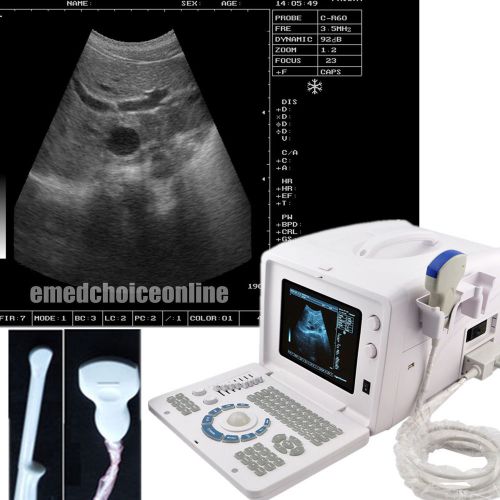

Digital Ultrasound Scanner+Convex Transvaginal 2 probe/option linear probe+3D CE

Digital Ultrasound Scanner Ultrasonic Diagnostic + Multi_frequency Convex + 3D

Laptop Note Full_Digital Ultrasound Scanner with Micro-convex Cardiac probe + 3D

Digital Laptop Ultrasound Scanner System Machine 5.0MHz Micro-convex Probe 3D

Digital Laptop Ultrasound Scanner Machine with 5.0 Micro-convex Probe + 3D + VGA